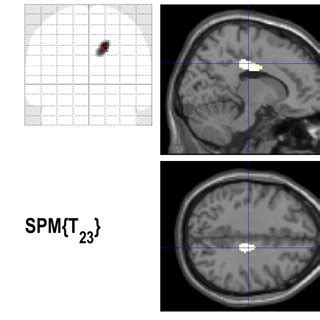

researchgate.net

Statistical Parametric Mapping Results | Download Scientific Di…

| An exemplary statistical parametric mapping (SPM) waveform displaying... | Download Scientific ...

320×320

Statistical Parametric Mapping (SPM) main …